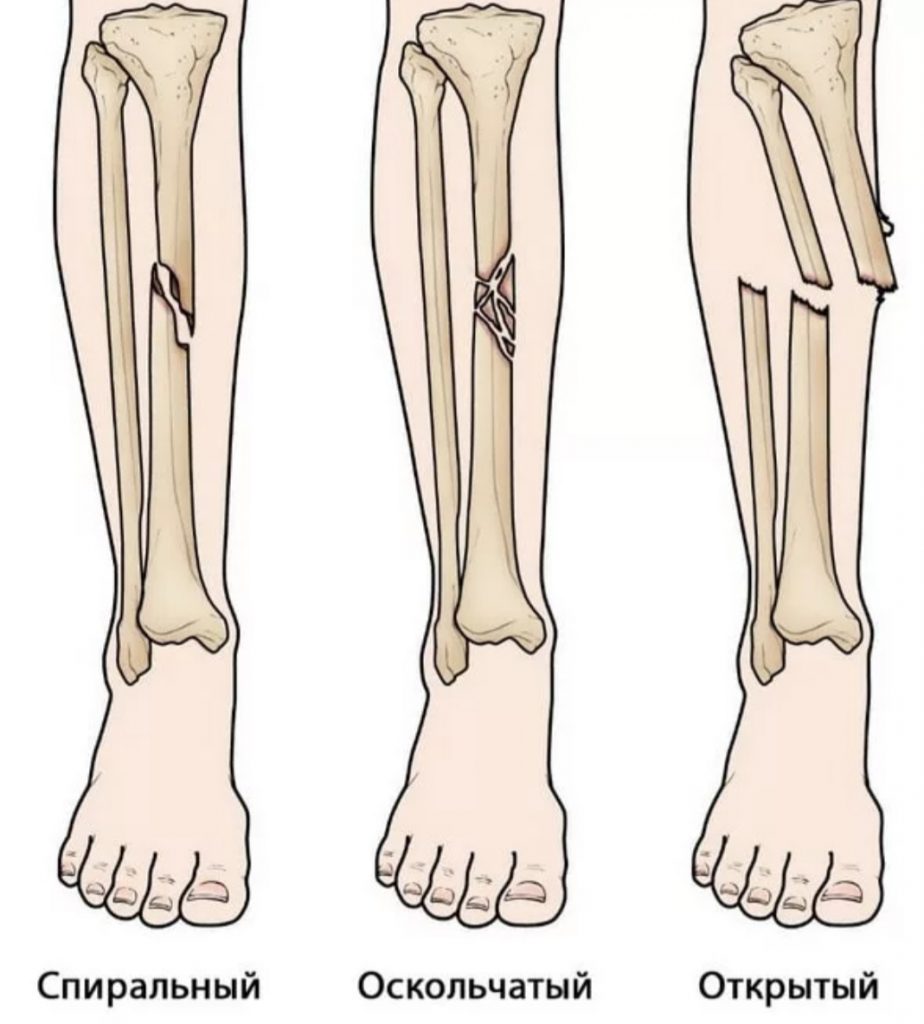

Перелом большой берцовой кости - серьезное повреждение, сопровождающееся болезненными ощущениями и нарушением функции ноги. На этой странице вы найдете много фотографий, позволяющих вам более детально изучить эту травму.

Здесь представлены медицинские изображения переломов большой берцовой кости, сделанные врачами в процессе диагностики и лечения. Вы сможете увидеть, как выглядит этот тип травмы на рентгеновских снимках и других медицинских изображениях.